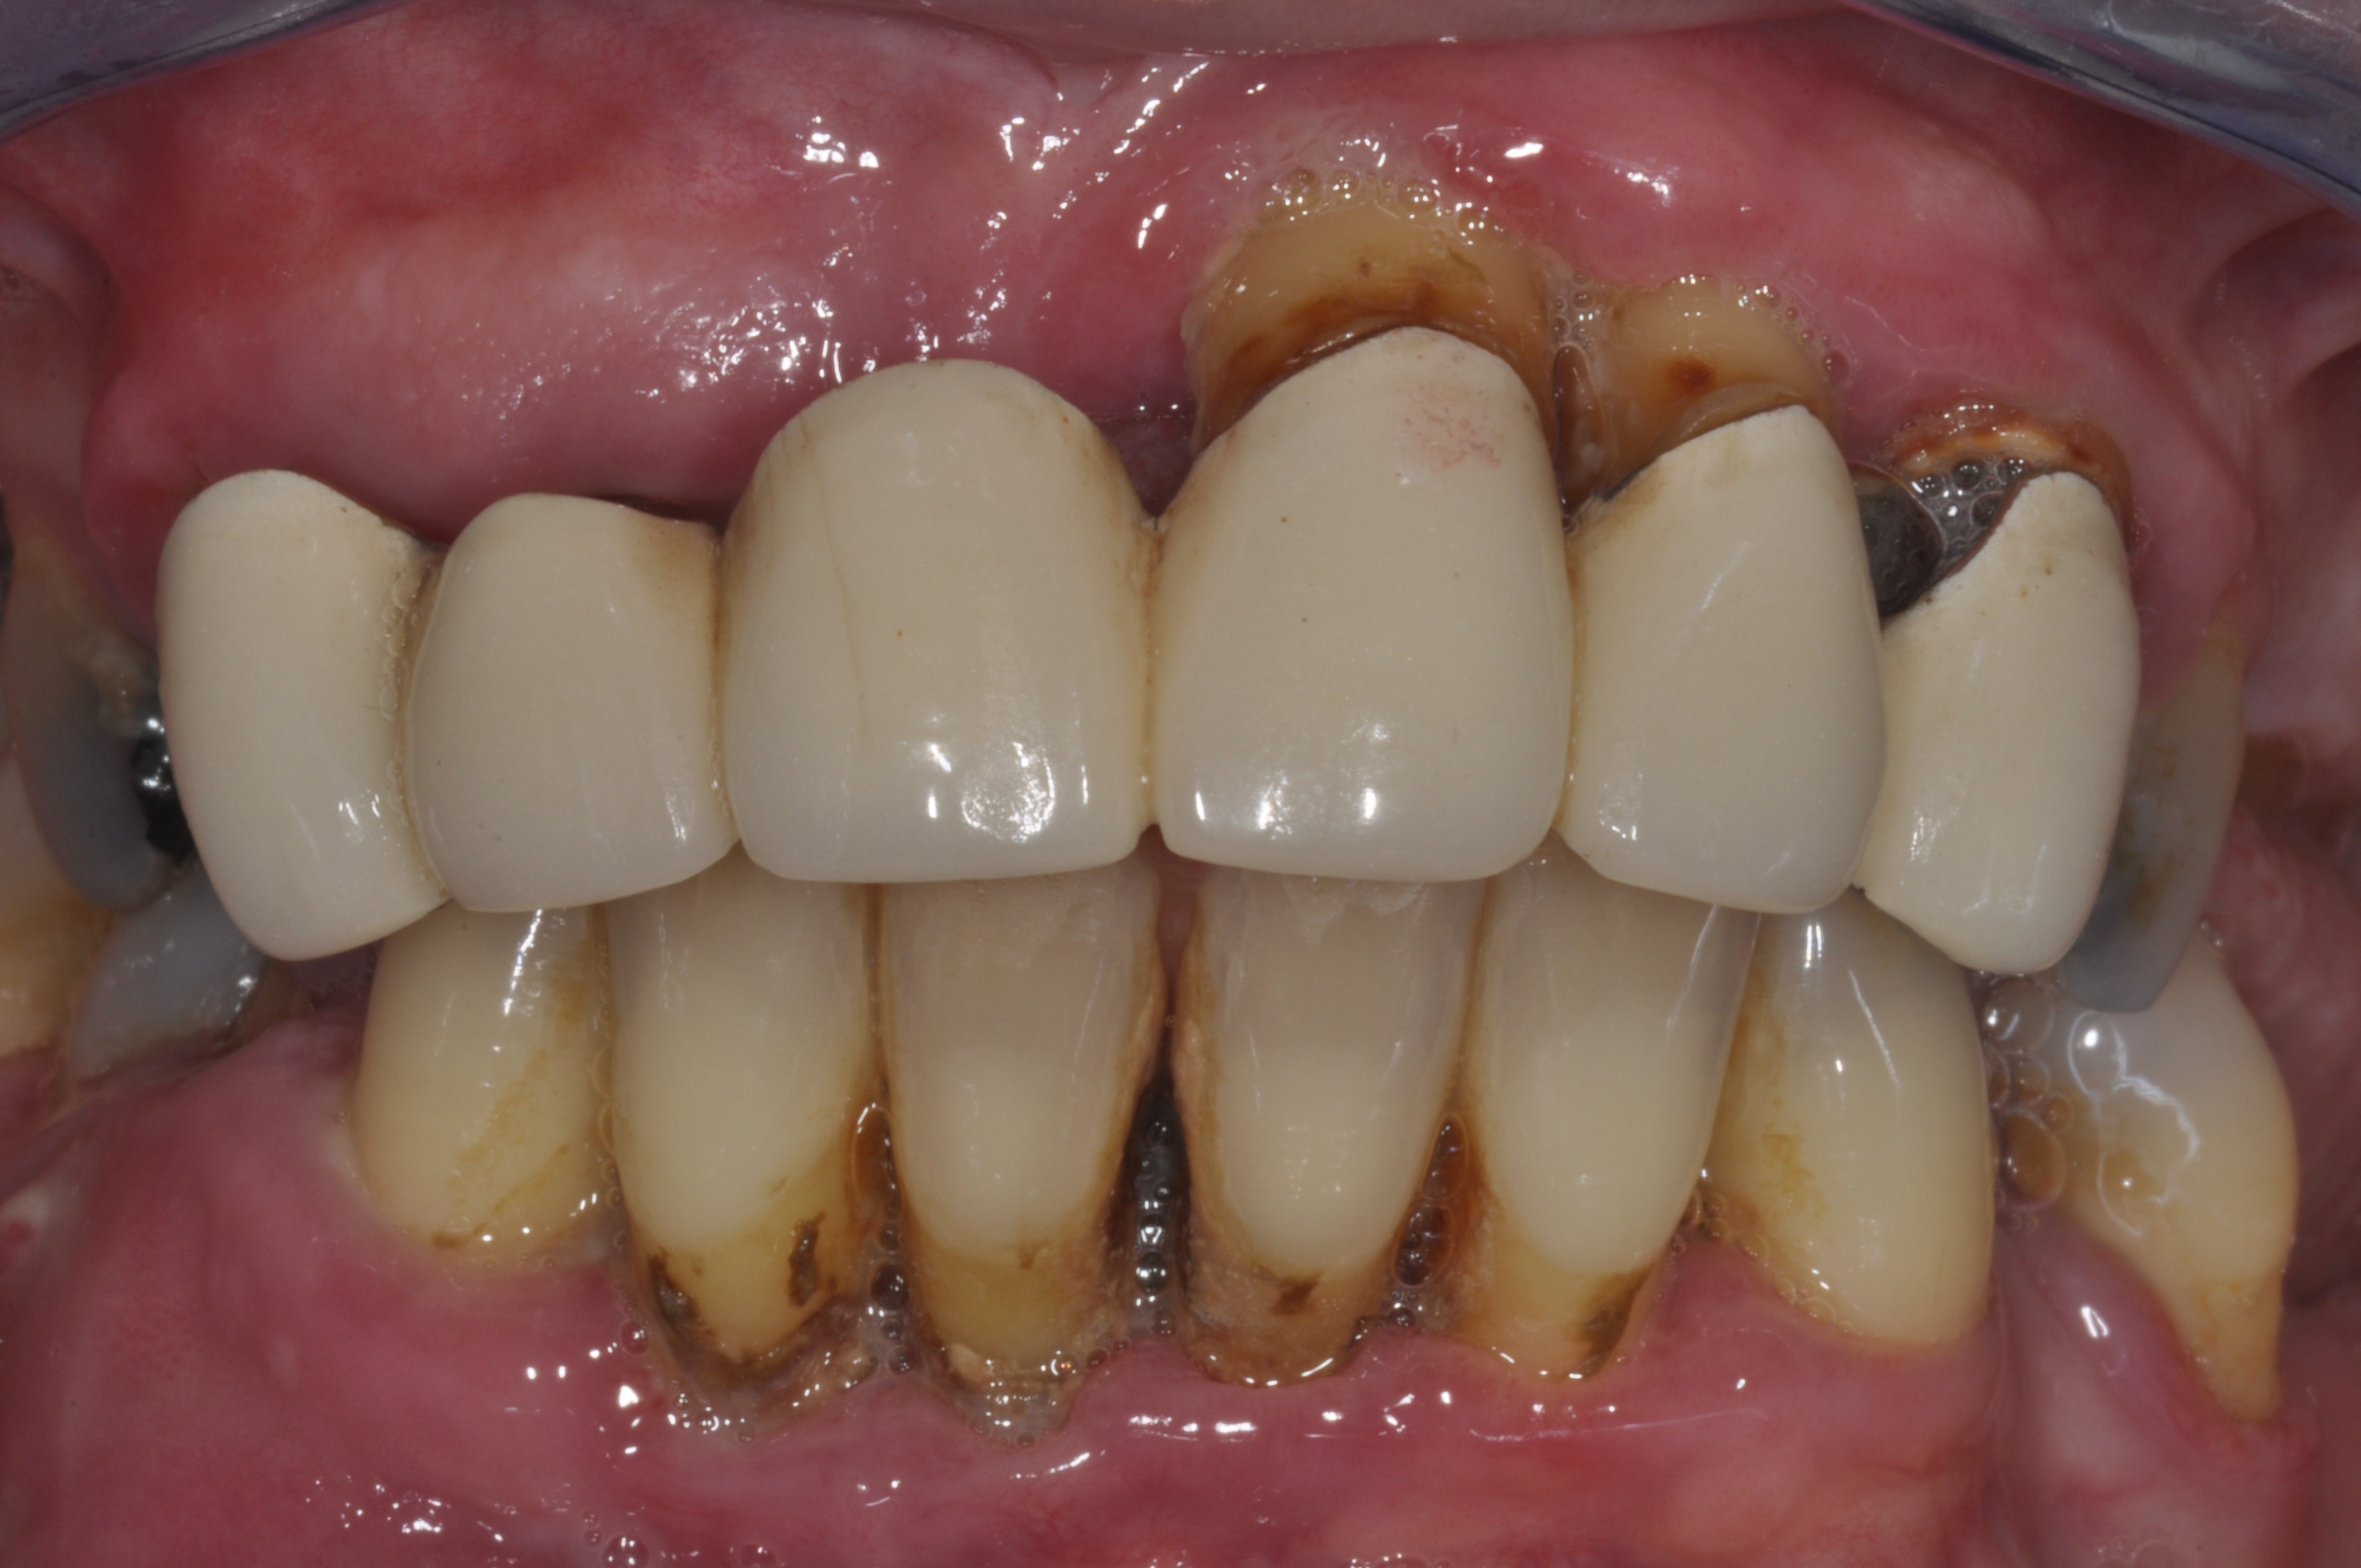

Unbefriedigende Ästhetik, vor allem aber Entzündungen im Knochen und eine massive Parodontitis mit bereits gelockerten Zähnen

Vorher: Unbefriedigende Ästhetik, vor allem aber Entzündungen im Knochen und eine massive Parodontitis mit bereits gelockerten Zähnen

Gesamtbehandlung in Sedierung: die Seitenzähne wurden durch Keramik-Implantate (Zahnentfernungen und Sofortimplantation) mit Knochenaufbau ersetzt; anschließend Gesamtüberkronung aus Vollkeramik mit Optimierung der Ästhetik

Nachher: Gesamtbehandlung in Sedierung: die Seitenzähne wurden durch Keramik-Implantate (Zahnentfernungen und Sofortimplantation) mit Knochenaufbau ersetzt; anschließend Gesamtüberkronung aus Vollkeramik mit Optimierung der Ästhetik